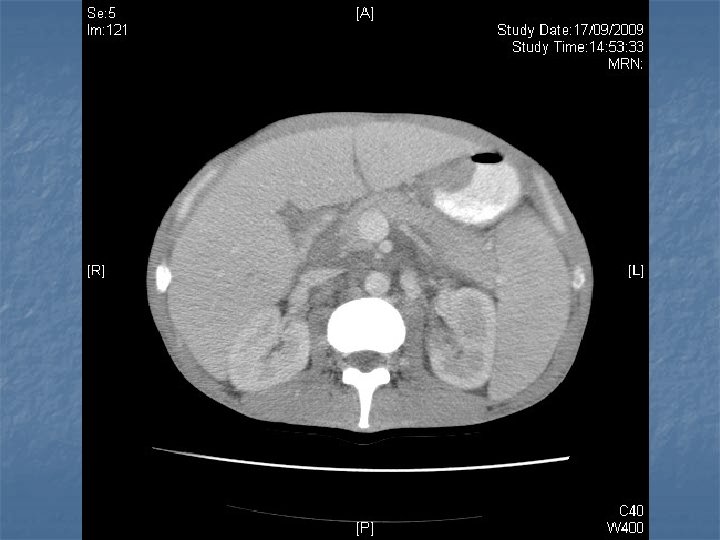

n n n PRETREATMENT INVESTIGATIONS: FBC, Renal and liver function, LDH, urate, Ig. GS. Histology review. Marrow aspirate+trephine (cytogenetics, immunology) CD 4 , HIV viral load. CT Scans. (MR Brain) (PET scan ) Echo / LVEF CMV, Hep B+C, Toxoplasma serology MAI screen. LP for CSF cytology +/- intrathecal Rx. (DLBC , Burkitt, Plasmablastic).